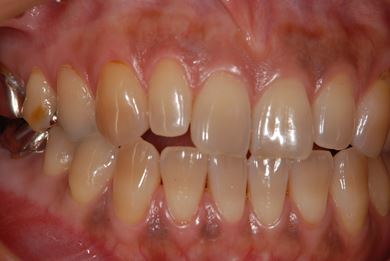

治療前

• 治療前